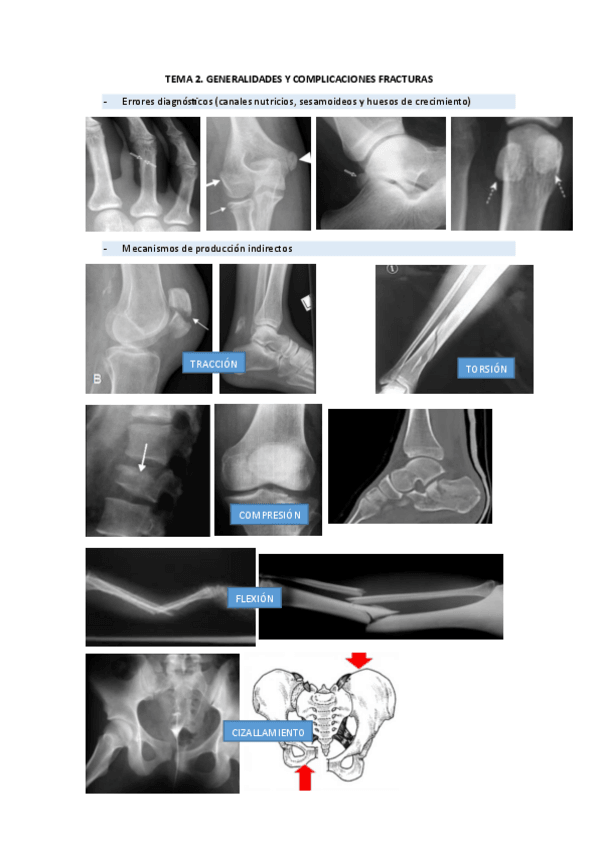

RADIOGRAFIAS PAT.QUIRURGICA

He publicado nuevos apuntes de 2º Patología Quirúrgica: RADIOGRAFIAS PAT.QUIRURGICA

rx-2.pdf

rx-1.pdf